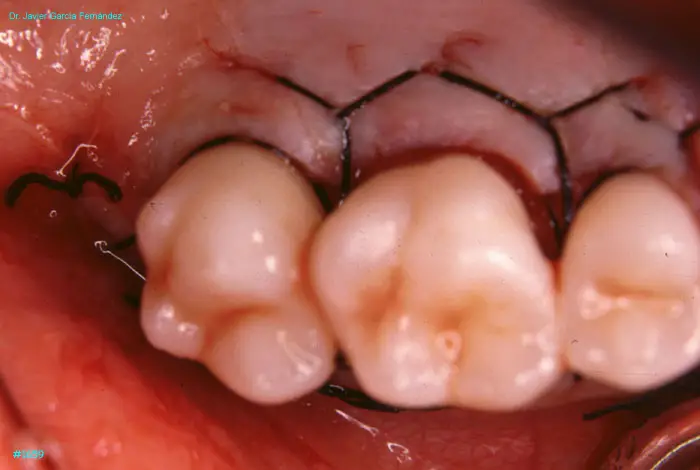

Atlas of Surgical Techniques in Periodontics. Chapter IV. Atlas de Técnicas Quirúrgica en Periodoncia

image 172